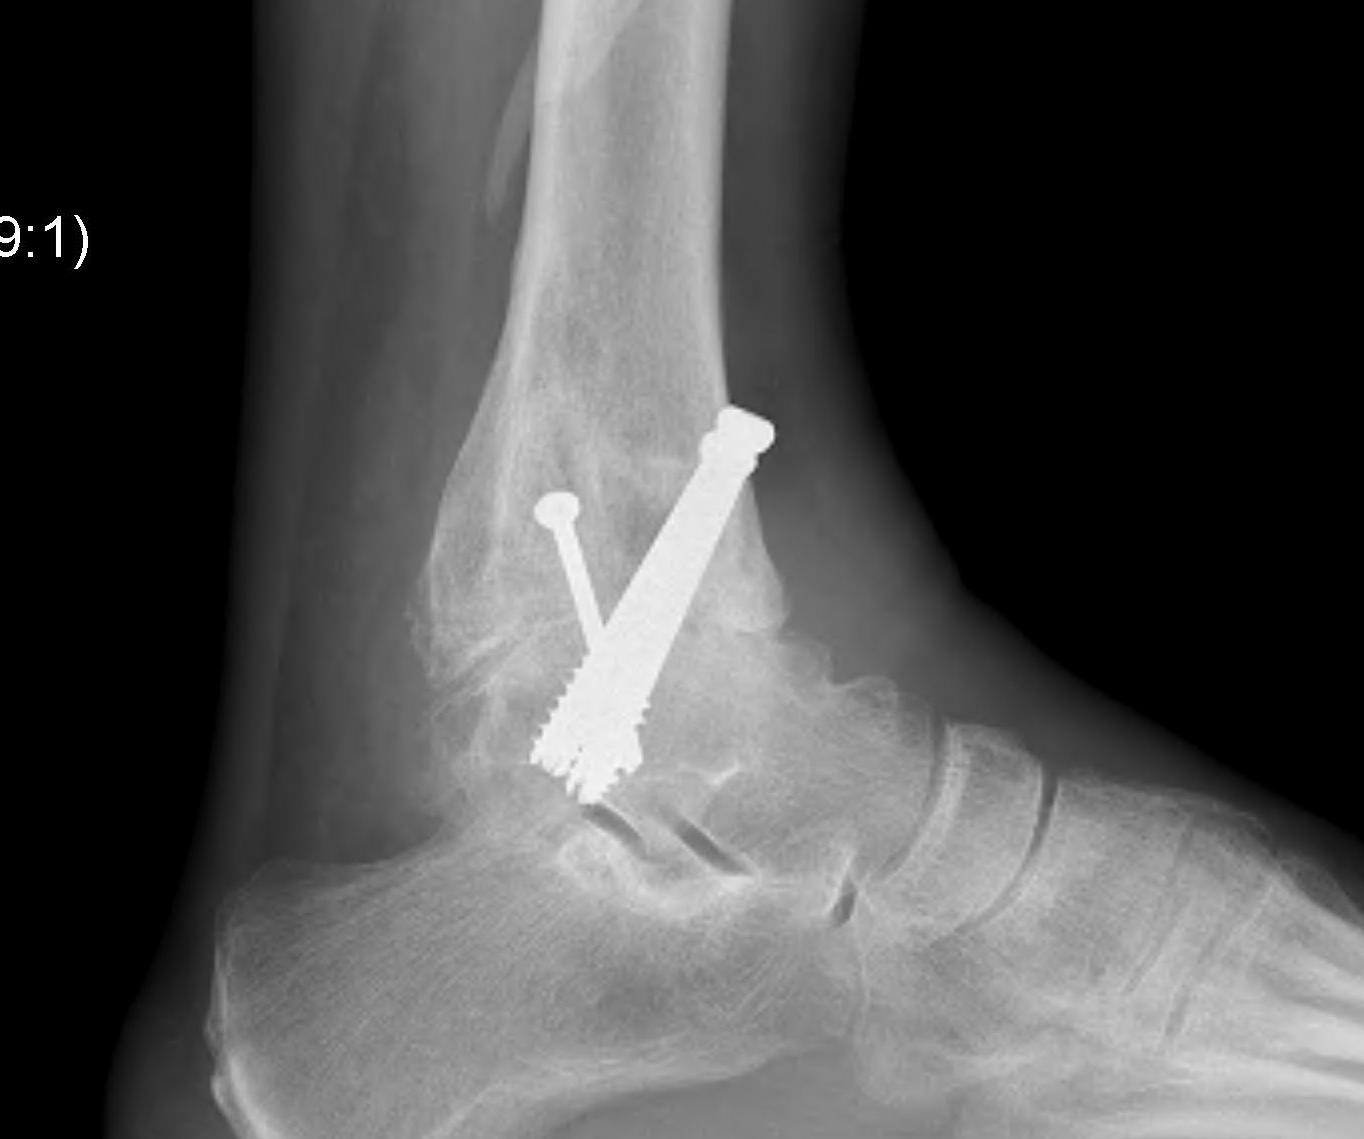

- two cannulated screws from medial tibia to talus dome / neck

- +/- screw medial malleolus to talus

- +/- screw fixation fibular / onlay graft

- fix with 3 x 6.5 mm cannulated screws

- 2 medial and one lateral